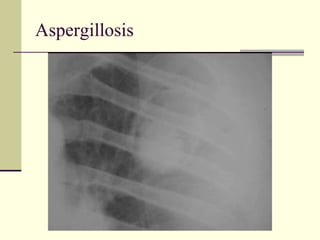

Cavities Containing Masses   1. Aspergillosis  2. Cavitating bronchogenic ca 3 Tuberculosis 4 Hydatid cyst

Aspergillosis